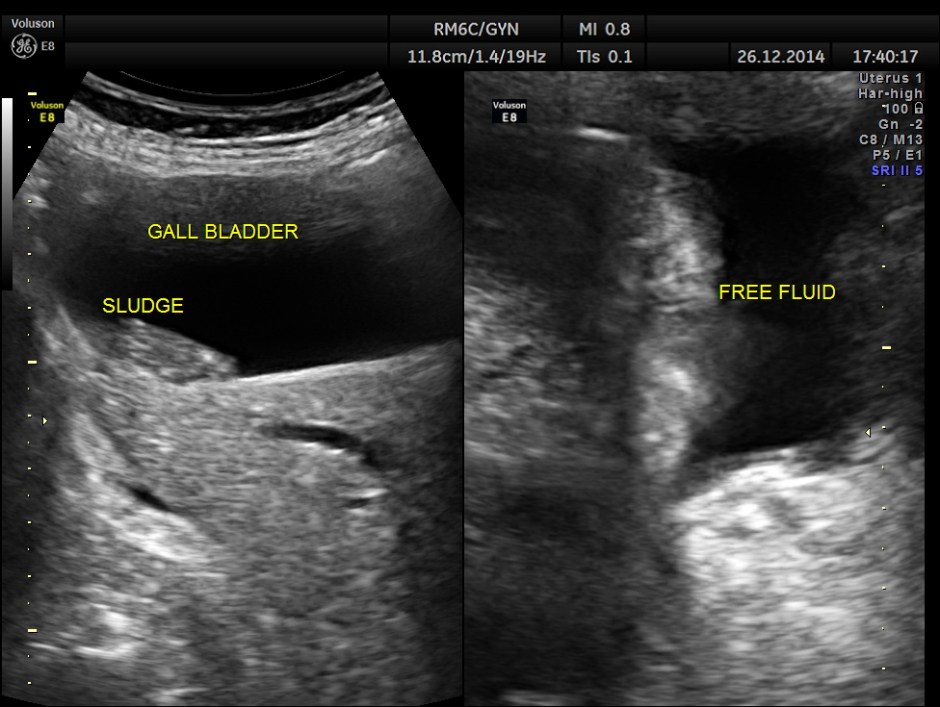

free fluid seen in the abdomen and pelvis , suggestive of possible peritoneal spread of Ca.

This was a case of Carcinoma of the head of the pancreas , causing biliary obstruction and also pancreatic ductal obstruction , with possible peritoneal deposits.